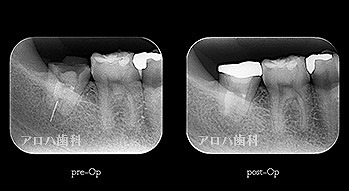

初回根管治療

1年予後

治療回数1回